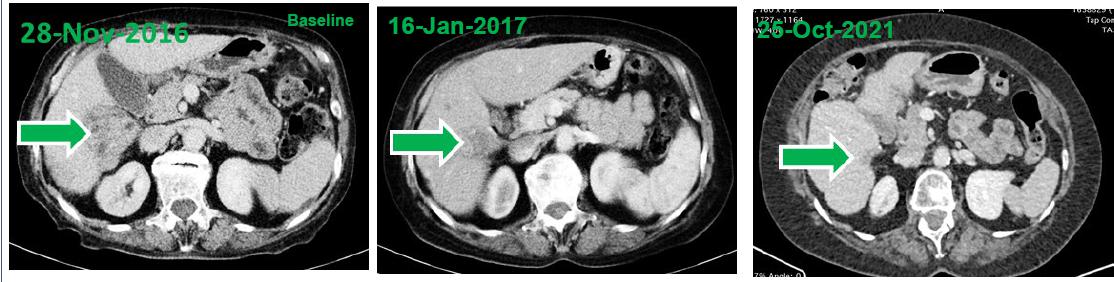

CT images of the tumor at baseline as well as 7 weeks and approximately 5 years after treatment initiation.

| · | At baseline, computed tomography (CT) scans demonstrated a large HCC tumor in the context of multifocal disease at baseline. Two treatment cycles later (e.g., after approximately 7 weeks) CT demonstrated shrinkage of the tumor mass that was consistent with a partial response. |

| · | Within 4 years of treatment, disappearance of the tumor mass, ascites and peritoneal carcinomatosis was observed consistent with a complete response by RECIST 1.1 and mRECIST. |

| · | At the time of reporting this case (5 years from treatment initiation), the response is ongoing as indicated by evaluation of liver functions and imaging studies. |